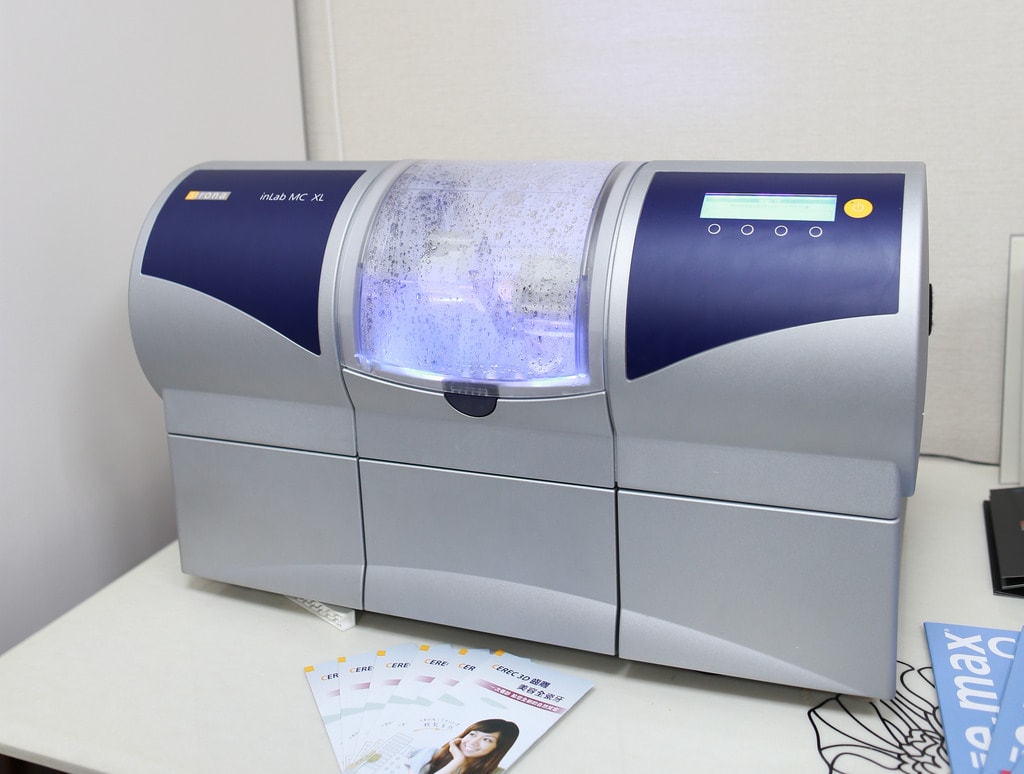

再來搭配這台搭配高精密且立即在短時間內的研磨機

德國CEREC 3D齒雕機採用精密的研磨系統,全自動化的研磨控制

提供快速與精確的研磨成果,平均一個修復體只需10分鐘即可完成

機器上也有製作時間顯示喔

短短時間內就製作完成啦!!